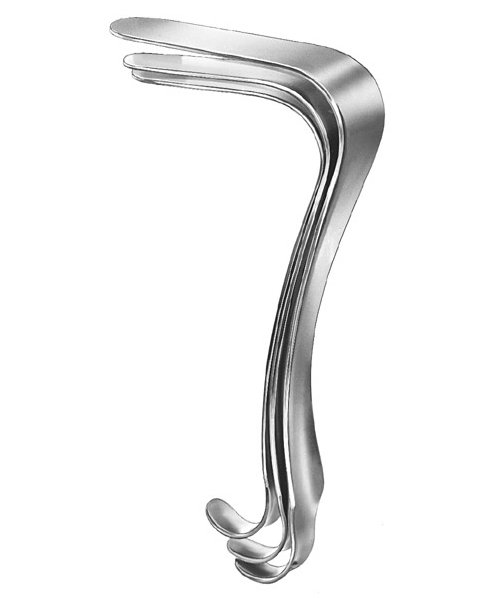

- Gynecology, Surgical Instruments

Endocervical Speculum

- Size : 25 CM - 9 3/4"

- Read more

-

- Gynecology, Surgical Instruments

Endocervical Speculum

- Size : 34.5 CM - 13 1/2"

- Read more